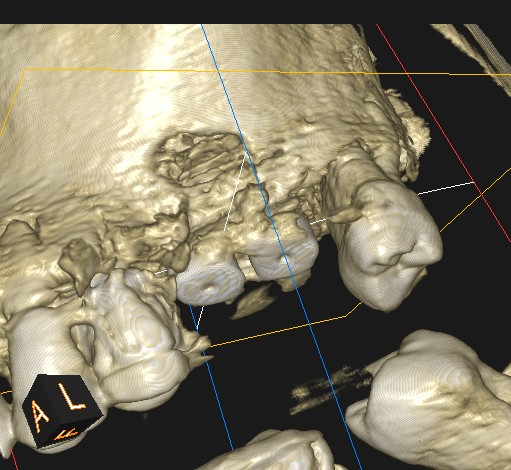

- CBCT helps us for the exact position of the window

- CBCT should guide the detachment of the sinus membrane

- Attention should be paid to any bone septa highlighted by the CT scan

CBCT